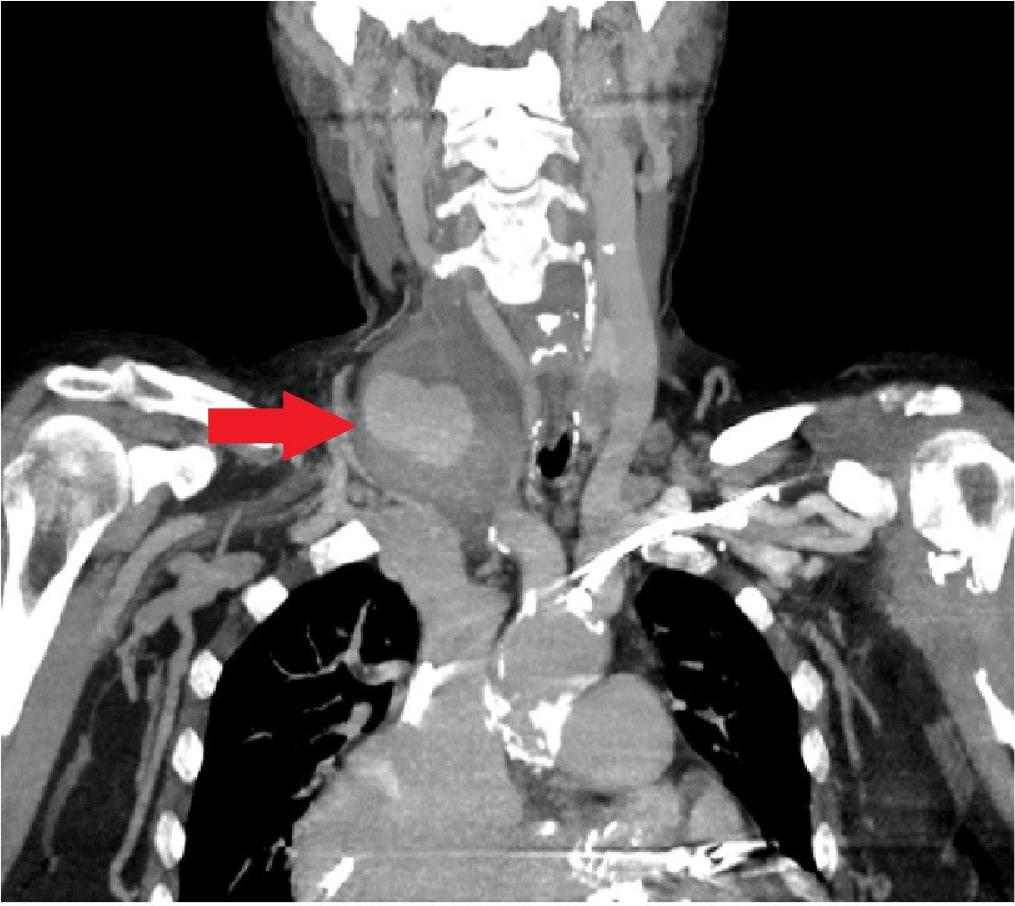

One month after TAVI, the patient presented to the emergency department with a right laterocervical pulsatile mass and newly developed hoarseness. An emergency computed tomography (CT) scan revealed a laterocervical hematoma extending into the mediastinum, with active bleeding causing a mass effect on adjacent structures (Figure 4). Surgical intervention was performed for bleeding control and drainage, while the anemic syndrome was corrected through blood transfusions with good outcome. The source of the bleeding was a pseudoaneurysm of a branch of the right subclavian artery, most likely developed due to central venous line manipulation during the prior hospitalization.

Computed tomography angiography shows a laterocervical pseudoaneurysm.